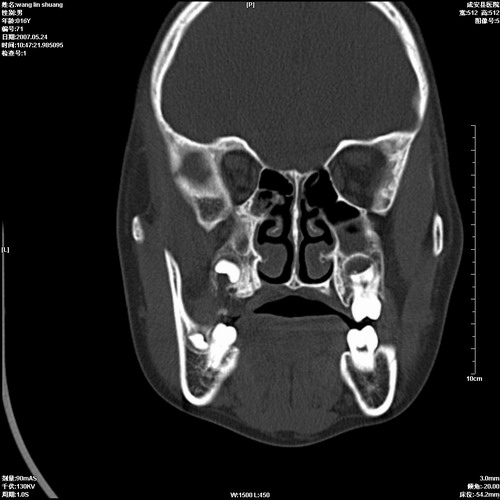

病人,男 16岁,鼻旁右肿胀,其余无不适感,ct图片

1、典型右侧根尖囊肿。

2、双侧上颌窦、筛窦、蝶窦炎

1\\左侧上颌骨含牙囊肿

2\\两上颌窦炎

右侧上颌骨含牙囊肿.双侧上颌窦炎症.

右侧上颌骨含牙囊肿.双侧上颌窦、蝶窦右侧炎症.

1、左侧上颌骨含牙囊肿。

典型的右侧上颌骨含牙囊肿,双侧上颌窦、右侧蝶窦炎症。